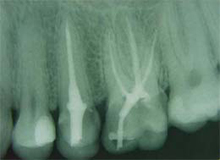

| Wenn der Zahn keine Schmerzen mehr aufweist, kann der "leere" Nervkanal abgefüllt werden. Das geschieht mit einer Paste und Guttaperchastiften (Guttapercha ist ein kautschukähnliches Material). Diese beiden verschließen den Kanal luftdicht, so dass keine neue Entzündung entstehen kann.